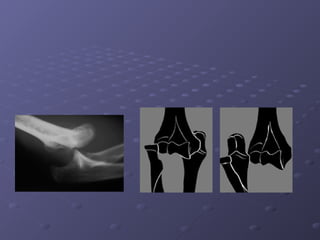

La luxation traumatique du coude plus fréquente chez

La luxation postéro- externe est la forme la plus

fréquente ; perte de contact entre l extrémité INF

de l humérus et les extrémités SUP du radius et du

cubitus qui sont luxes en arrière

Diagnostic clinique

- Douleur.

- l'impotence du coude est totale

- Gonflement.

- Bras en extension.

-Déformation :

- Raccourcissement de l'avant-bras.

- Saillie de l extrémité INF l'humérus en avant du

coude.

- Saillie de l'olécrâne en arrière du coude

La palpation permet de faire le diagnostic

Les repères anatomiques normaux du coude ne sont

plus à leur place normale (triangle équilatéral)

La trochlée humérale luxée est palpée en avant et la

tète du radius en arrière et en dehors